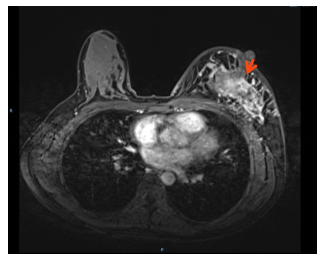

1.乳腺增强MRI:左侧乳腺多发肿块,形态不规则呈分叶状,边缘毛刺,内部呈不均匀混杂强化,病灶最大直径约7.2cm(靶病灶1)。(图1)

图1. 乳腺增强MRI